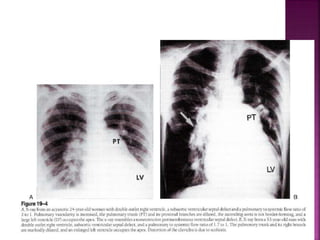

 CXR in DORV sub Ao VSD low PVR similar to

non restrictive peri mem VSD with high Qp

 Thymus is present in DORV TGA end of spectrum

unlike D-TGA wherein thymus typically absent

 Pulmonary trunk prominent (side by side

arteries)

 LA LV prominent in volume overload

 RA RV prominent with CCF

 Lung fields oligemic before fall in neonatal PVR

and with onset of pulmonary vascular disease

(semblance with non res VSD with EISENMENGER)